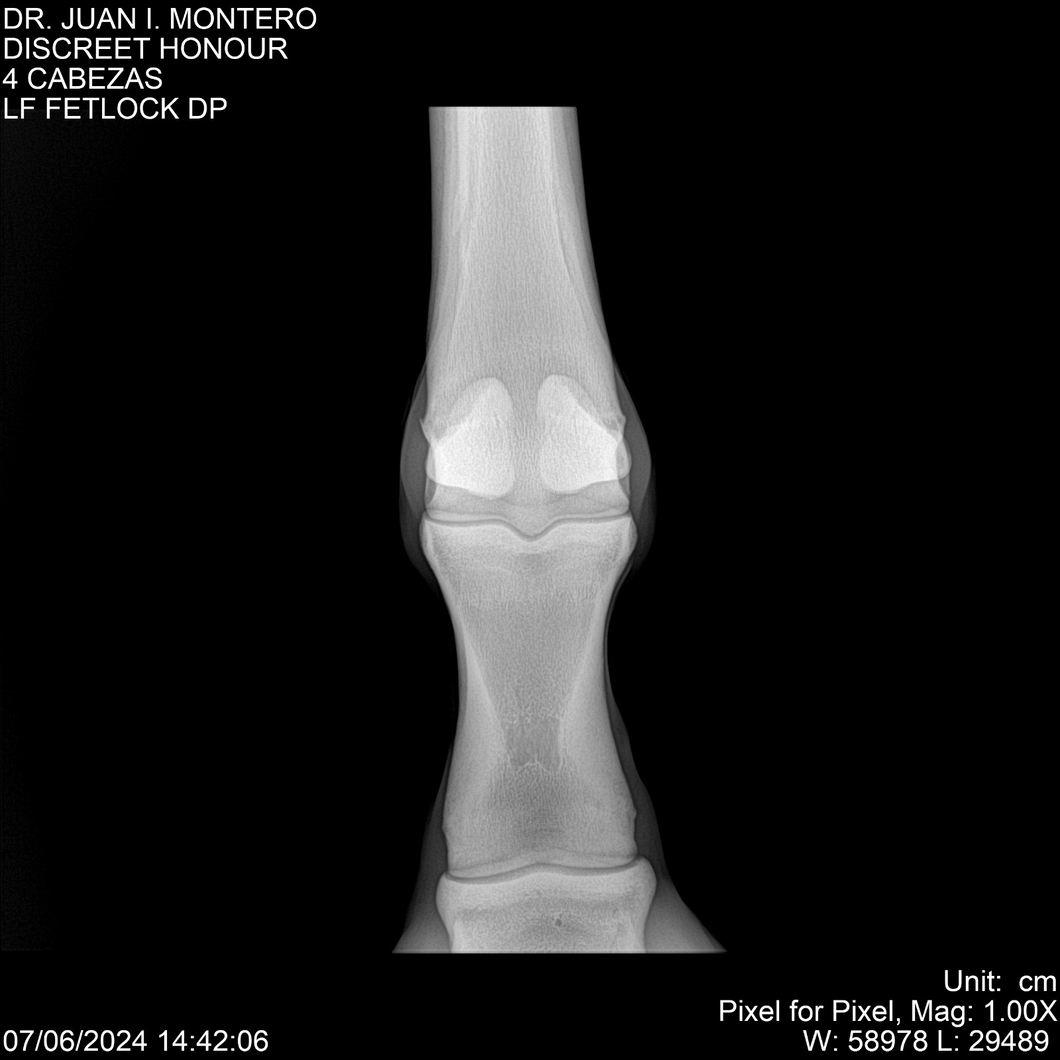

LOTE 6, DISCREET HONOUR 🔥 🔥 🔥 Lote Anterior Volver al remate Lote Siguiente Ficha Contacto Montevideo - Ficha del Lote Identificador: #281093 Categoría: Yeguarizos Montevideo - 82 Visualizaciones ClicData Contacto Empresa: Abelenda N. R., Walter Hugo Nombre*: Teléfono* : E-mail* : Mensaje Enviar Registrese gratis Este contenido Exclusivo está disponible sólo para usuarios registrados Ingresar